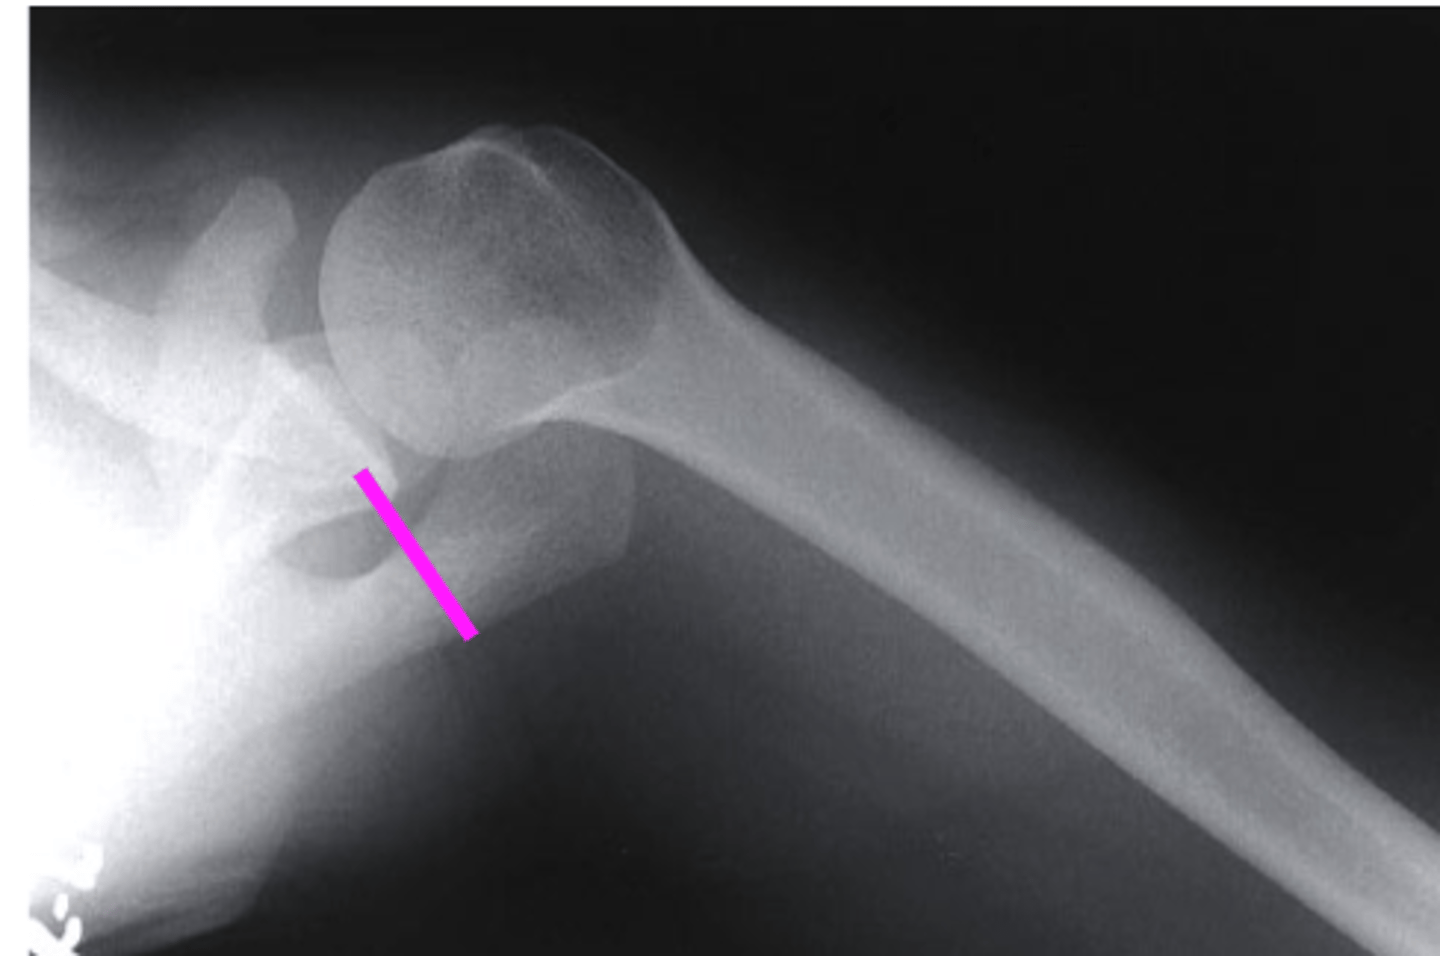

AP + IR

what view is this?

clavicle

what does the pink line point to?

spine of scapula

coracoid process

glenoid fossa of scapula

AC joint

acromion

Humeral Head

lesser tubercle